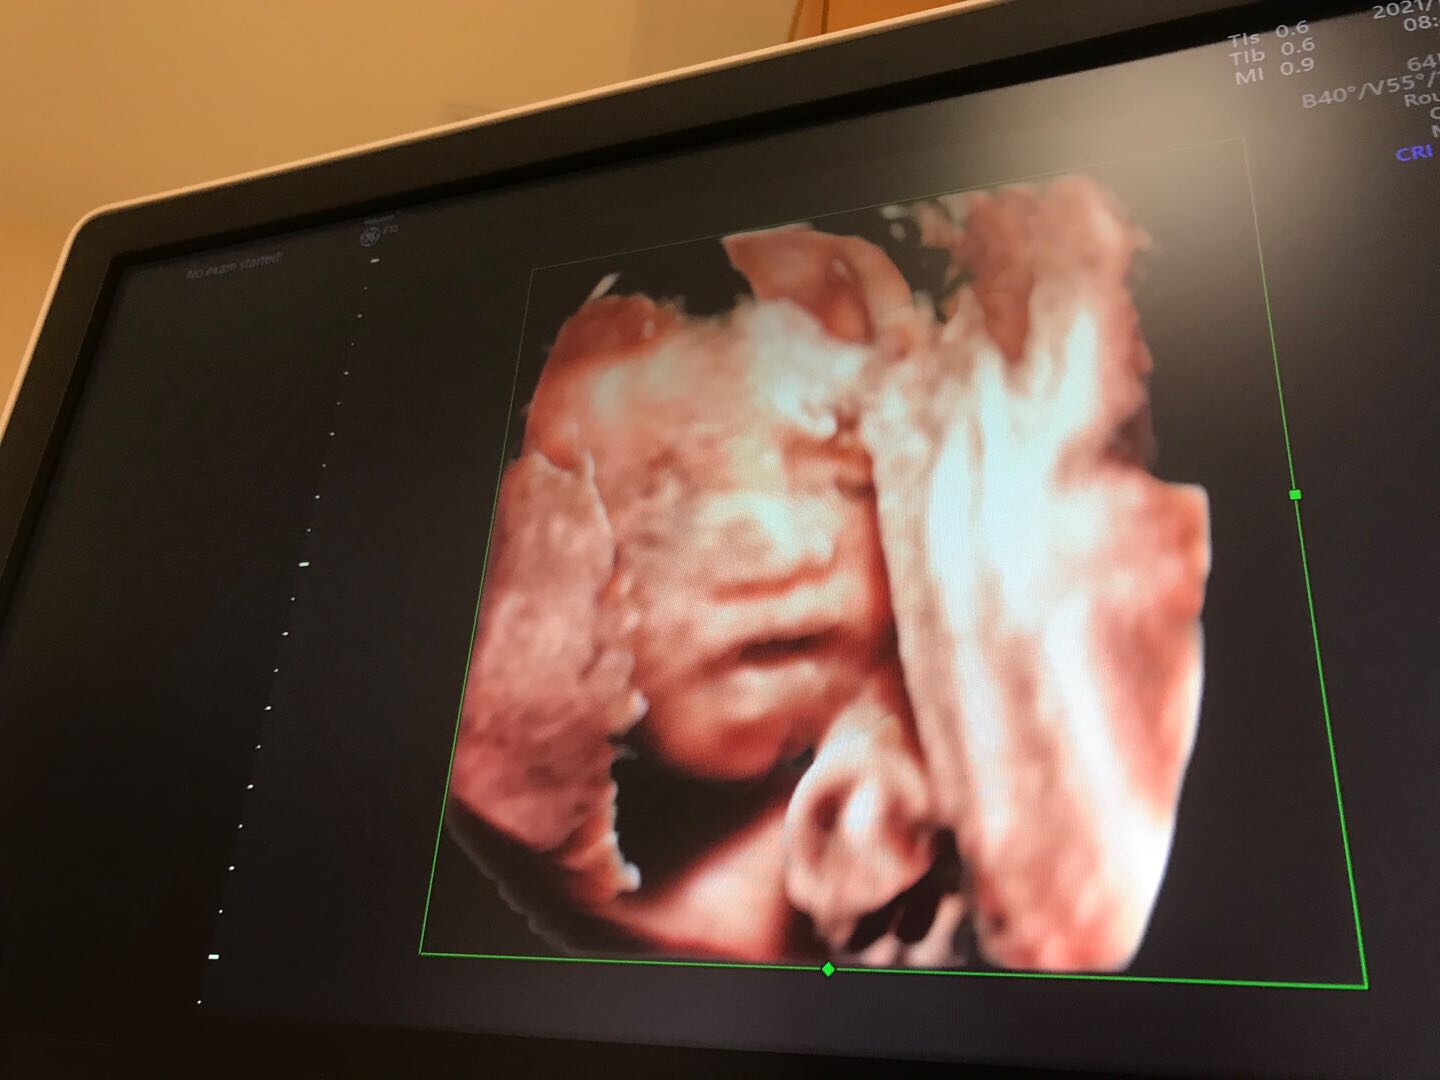

宝宝头上这是啥四维彩超医生说正常的